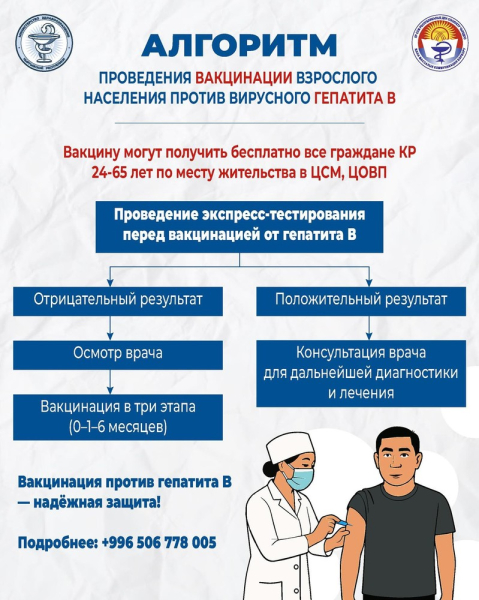

Тестирование на вирусные гепатиты В и С доступно в центрах семейной медицины и общеврачебной практики по месту жительства.

При положительном результате пациента направляют на подтверждающее обследование и лечение.

Бесплатно вакцинироваться могут взрослые 24-65 лет и все, кто не получал прививки ранее. Вакцина вводится в 3 этапа (0–1–6 месяцев) и обеспечивает длительную защиту.